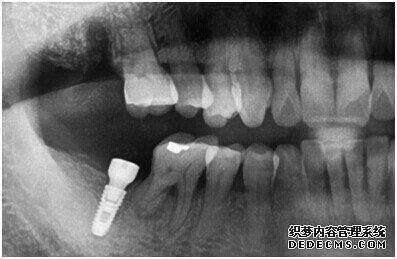

种植设备检查牙齿

成功植入种植体后的效果图

种植体成功植入后的CT效果图

整个种植牙完成后的效果图